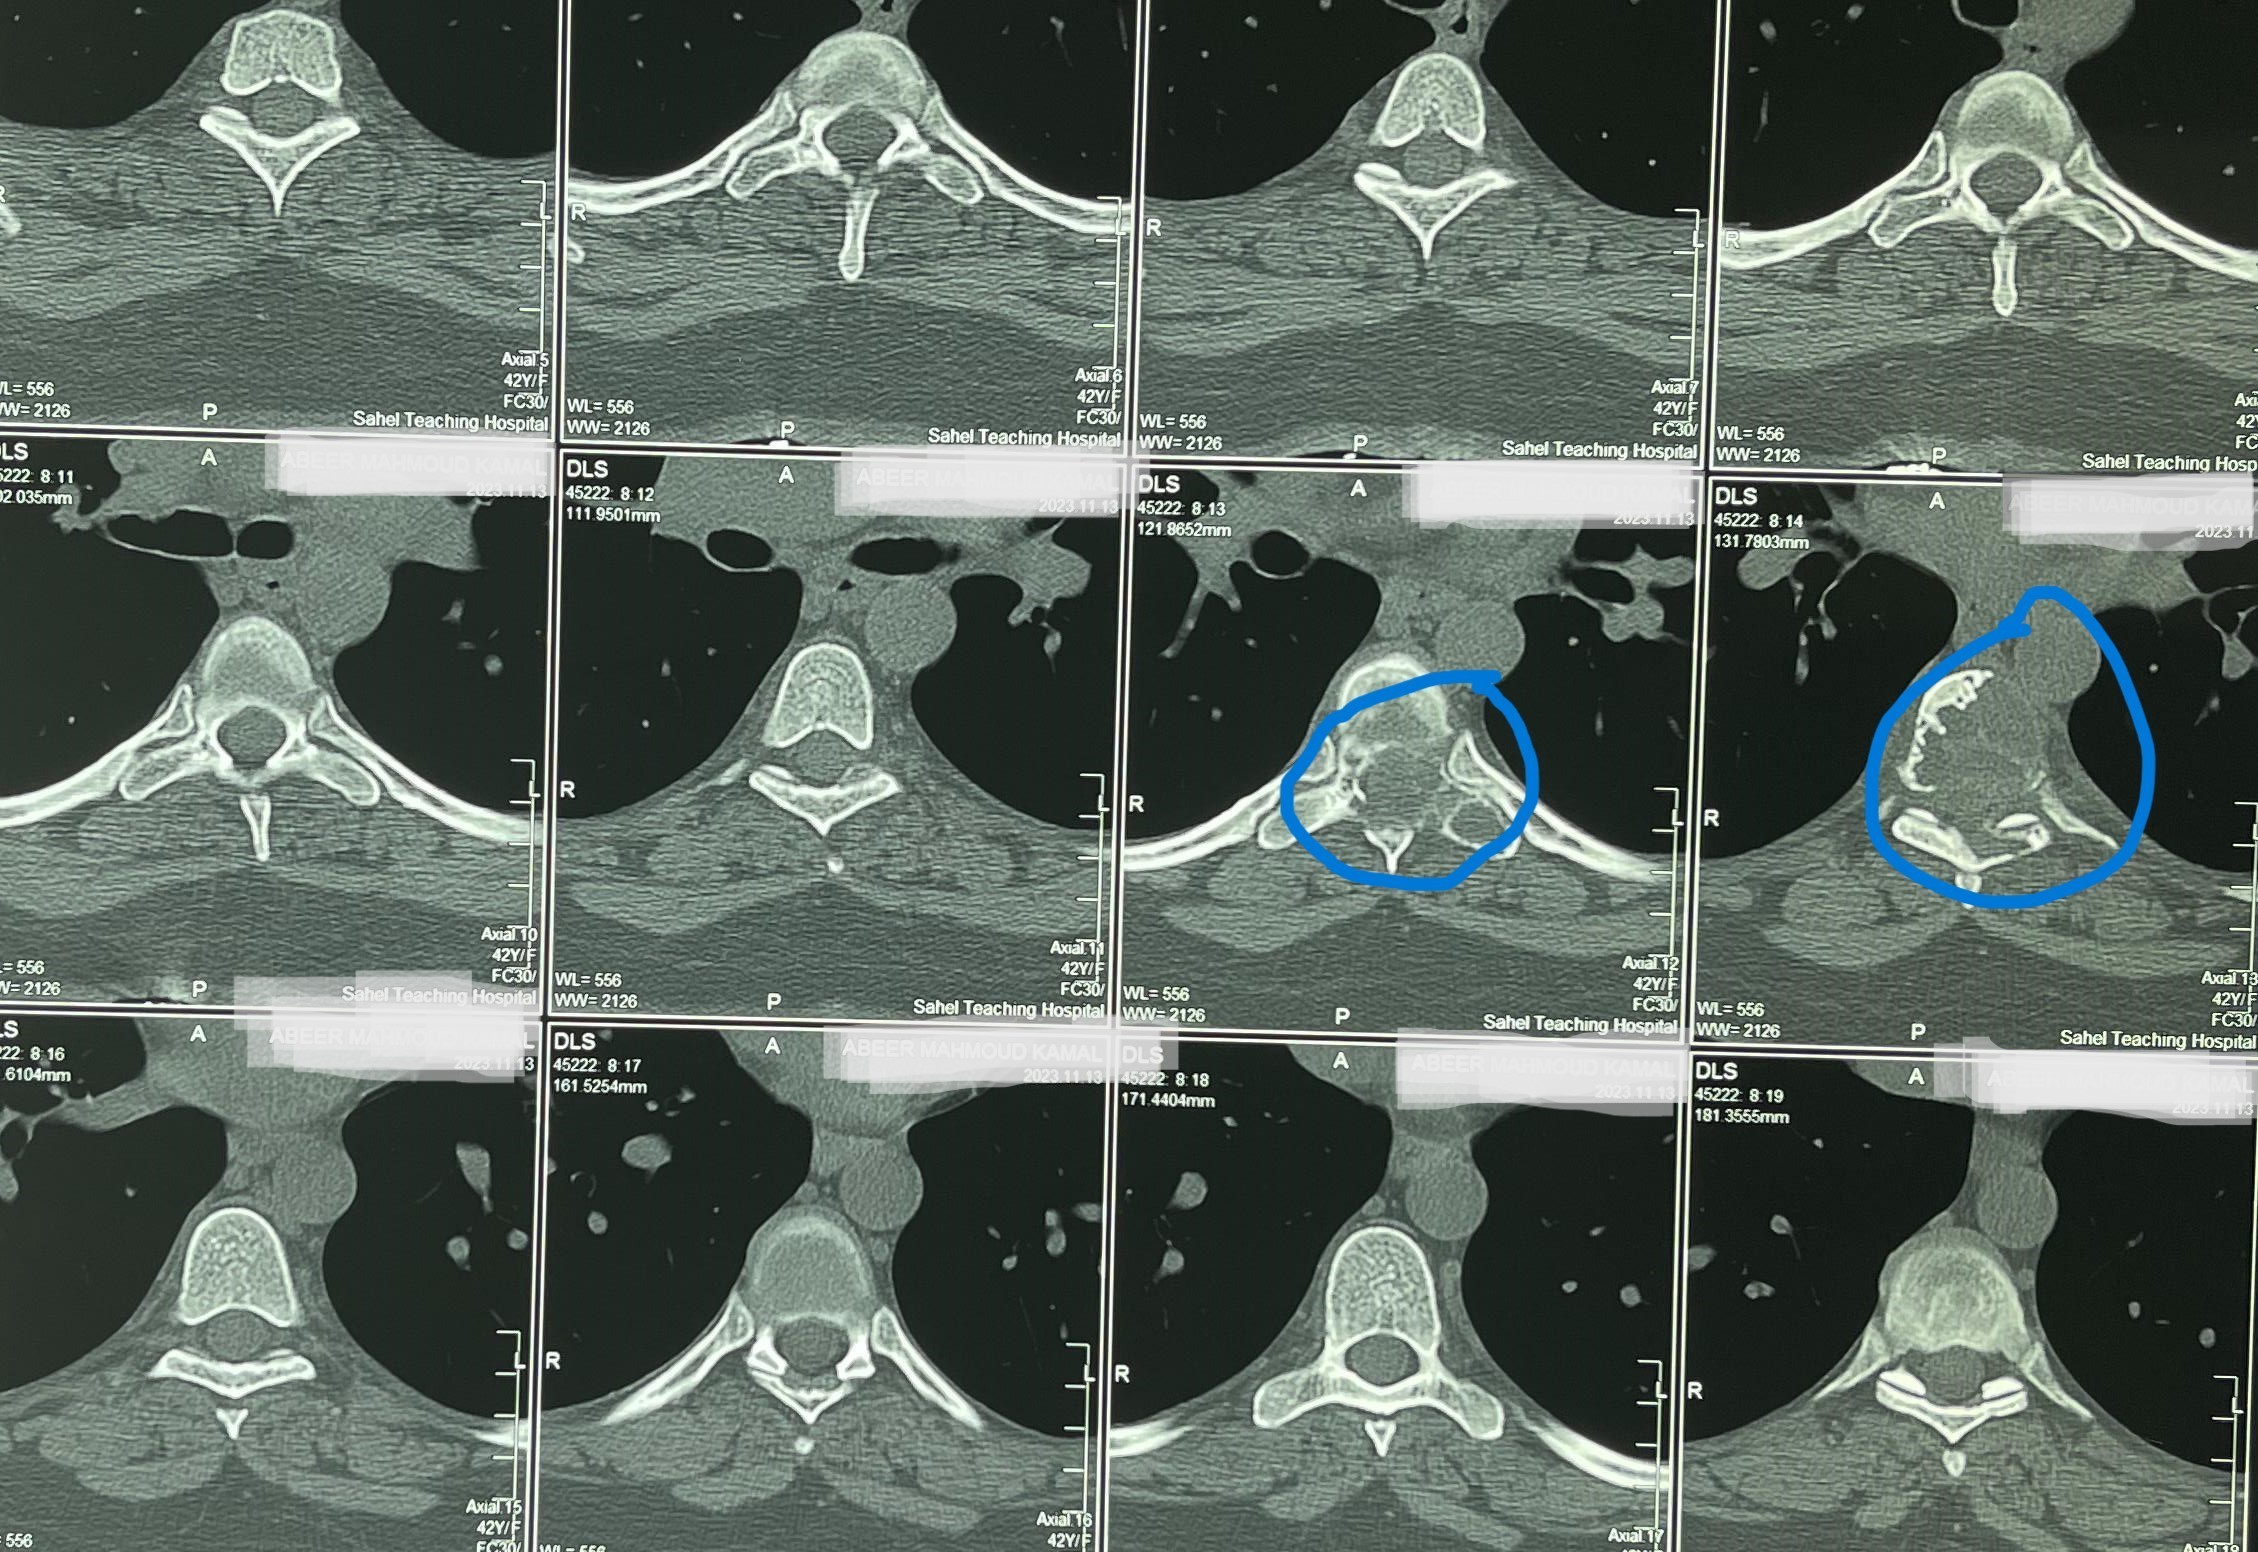

مريضة عمرها 43 عام تعاني من ضعف متزايد بالطرفين السفليين.

43-year-old female patient suffers from increasing weakness in the lower extremities

A 43-year-old woman suffering from progressive weakness in both lower limbs was diagnosed and treated. This condition affects walking ability and mobility, requiring thorough neurological evaluation to determine the underlying cause and develop an appropriate treatment plan.

• Accurate diagnosis using latest neuroimaging techniques